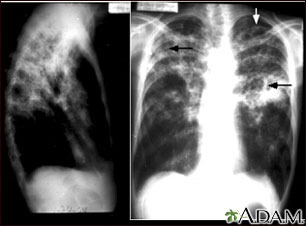

A chest x-ray is an x-ray of the chest, lungs, heart, large arteries, ribs, and diaphragm.

It may also be done if you have signs of tuberculosis, lung cancer, or other chest or lung diseases.

A serial chest x-ray is one that is repeated. It may be done to monitor changes found on a past chest x-ray.

What Abnormal Results Mean

Abnormal results may be due to many things, including:

In the lungs:

- Collapsed lung

- Collection of fluid around the lung

- Lung tumor (noncancerous or cancerous)

- Malformation of the blood vessels

- Pneumonia

- Scarring of lung tissue

- Tuberculosis